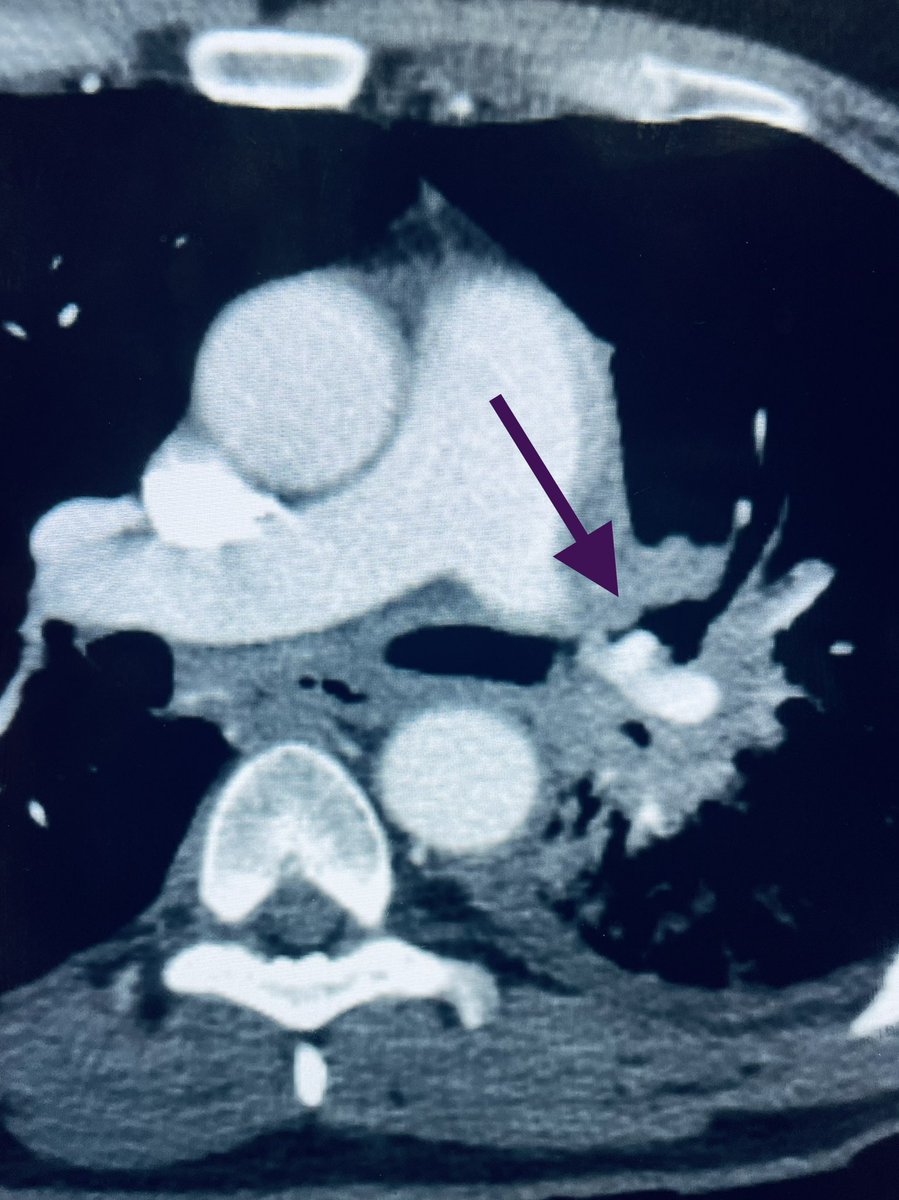

New study @AnnalsofIM bit.ly/2Km3KYu by @DrTalenfeld @WeillCornell: Percutaneous ablation for T1a #renalcancer has similar 5-year survival rates to radical nephrectomy but with far fewer 30-day complications and less #kidneyfailure.